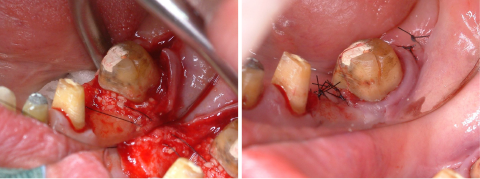

術前および術後の比較

before before |

after after |

矯正治療開始前及び矯正治療終了時の口腔内写真とレントゲン写真です。

歯肉形成外科の術中所見です。最終的は被せもののイメージを行いながら歯茎と顎の骨の整形を行いました。

before before |

after after |

術前と術後の比較写真です。

歯茎の下の方まで虫歯でしたが歯茎の上までしっかりと健康な歯の部分を出すことができました。